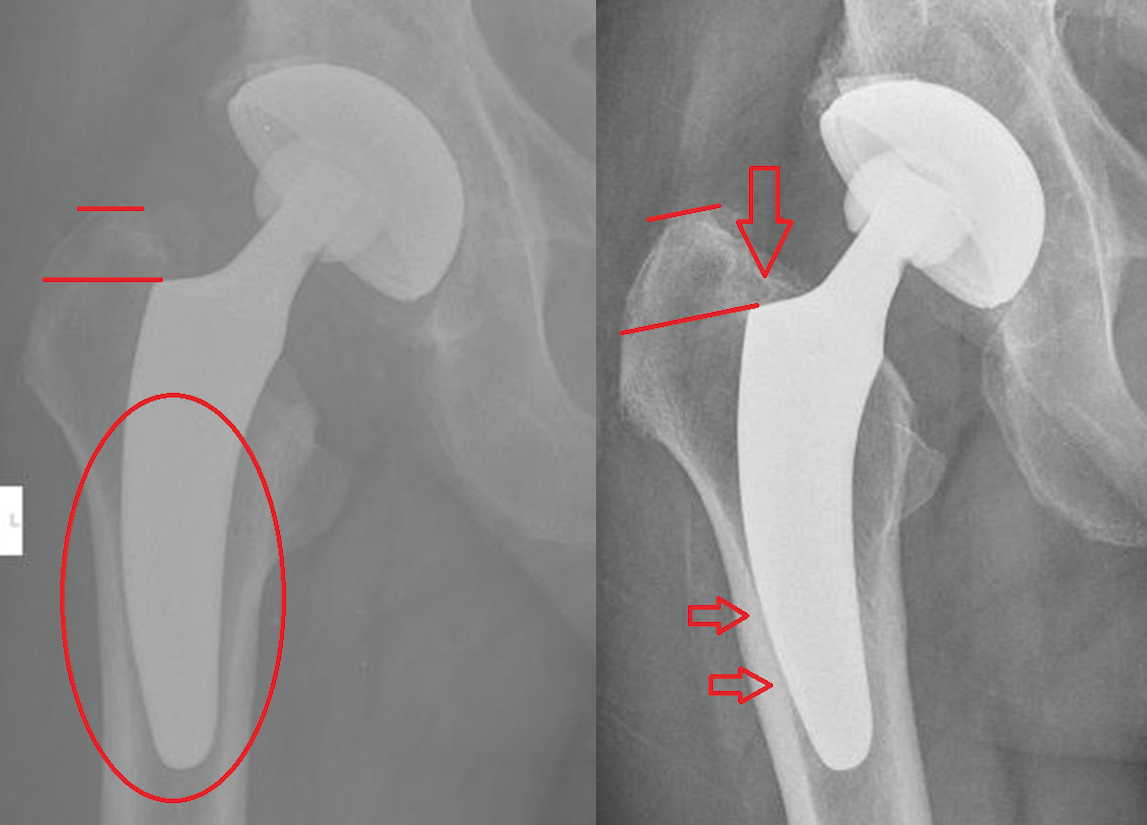

Given a shortening of stem length in calcar-guided short-stem THA, primary stability potentially causes concerns [20] Bieger R, Ignatius A, Decking R, et al. (2012) Primary stability and strain distribution of cementless hip stems as a function of implant design. Clin Biomech (Bristol, Avon) 27:158–64. doi: 10.1016/j.clinbiomech.2011.08.004.. The predominant type of fixation is metaphyseal anchoring, based on the fit-and-fill principle. However, due to the option of individualized positioning of these stem-designs, the type of anchoring differs distinctly. In varus alignment three-point anchoring is common with cortical contact to the lateral cortex of the partially resected neck, the medial calcar, and the lateral cortex at the tip of the stem. However, depending on positioning and sizing, especially in extensive valgus alignment, pronounced diaphyseal anchorage is possible. In those cases, a securely achieved cortical contact to the distal lateral cortex, as well as to the distal medial cortex is crucial. In valgus position a missing cortical contact of the tip has been frequently observed in the early collective including the learning curve, particularly in cases of undersizing. Therefore, surgeons should take into account that particularly in valgus hips, undersizing accompanied with a lack of contact to the lateral cortex, might cause initial instability and subsequent implant micromovement [16] Kutzner KP, Freitag T, Donner S, et al. (2017) Outcome of extensive varus and valgus stem alignment in short-stem THA: clinical and radiological analysis using EBRA-FCA. Arch Orthop Trauma Surg 137:431–439. doi: 10.1007/s00402-017-2640-z. (Figure 7). The usage of intraoperative fluoroscopy to identify undersizing of the stem is therefore highly recommended [14], Kutzner KP, Pfeil J (2018) Individualized Stem-positioning in Calcar-guided Short-stem Total Hip Arthroplasty. J Vis Exp. doi: 10.3791/56905[19] Loweg L, Kutzner KP, Trost M, et al. (2017) The learning curve in short-stem THA: influence of the surgeon’s experience on intraoperative adjustments due to intraoperative radiography. Eur J Orthop Surg Traumatol 1–7. doi: 10.1007/s00590-017-2049-y..